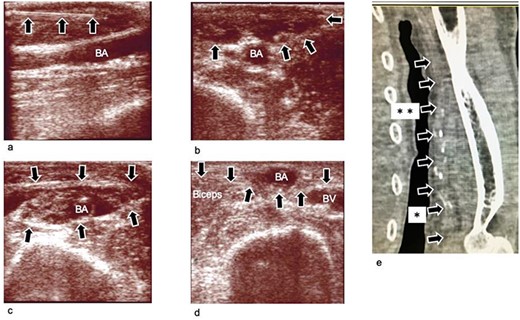

Ultrasound images obtained during and after the operation, (a) Ultrasound image obtained during infusion of TLA solution into subcutaneous tissue. The needle is clearly seen (arrow mark). (b) Ultrasound image obtained after infusion of the TLA solution into the subcutaneous tissue. The subcutaneous tissue becomes edematous (arrow mark). (c) Ultrasound image obtained after infusion of the TLA solution around the BA. The compartment becomes edematous. The BA is dissected from the fascia surrounding it. (d) Ultrasound image obtained 3 weeks after the operation. The BA is transposed to the subcutaneous layer, which is superficial to the brachial fascia (arrow). (e) Plane computed tomography image obtained 4 weeks postoperatively. The BA (arrow marks) is transposed to the subcutaneous layer. The transposed lesion was between arrow marks with * and **. The transposed length was 10 cm, and the depth of the lesion was 2 mm, which was just beneath the skin. BA: brachial artery; BV; brachial vein; TLA: tumescent local analgesia.